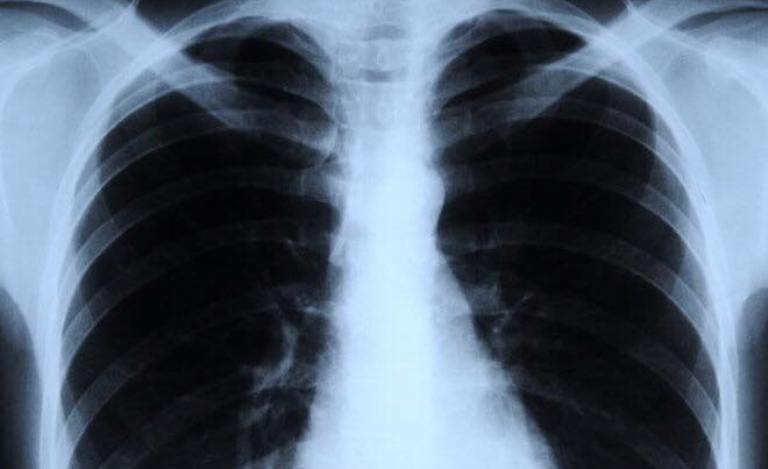

पाल्पा । पाल्पाको पूर्वखोला गाउँपालिकाले निःशुल्क भिडियो एक्स– रे तथा जनस्वास्थ्य प्रयोगशाला सेवा सुरु गरेको छ।

रिङ्गनेरह स्वास्थ्य चौकीमा स्थापना गरिएको सो सेवा प्रत्येक महिनाको एक दिन घुम्ती शिविरको आयोजना गरी वडावडाका स्वास्थ्य संस्थामार्फत सेवा दिने उद्देश्यले भिडियो एक्स–रे तथा जनस्वास्थ्य प्रयोगशाला स्थापना गरिएको स्वास्थ्य शाखा प्रमुख मोहन ढकालले जानकारी दिए।

नागरिकको स्वास्थ्य आधारभूत आवश्यकता रहेकाले पालिकाले त्यसलाई प्राथमिकतामा राखेर प्रदेश सरकारसँग समन्वय गरी भिडियो एक्स–रे सेवाको सुरुआत गरिएको गाउँपालिकाका अध्यक्ष नुनबहादुर थापाले बताए।

सामान्य एक्स–रे र रगत जाँचकै लागि उपचार शुल्कभन्दा बढी यातायात शुल्क तिरेर सदरमुकाम जानुपर्ने बाध्यता थियो। भिडियो एक्स–रे र प्रयोगशाला सेवा लिन तानसेन जानुपर्ने समस्या अब हटेको छ।

गाउँपालिकाको स्वास्थ्य शाखाको यही चैत ७ गतेसम्मको तथ्याङ्कअनुसार ११२ जना गर्भवती पालिकाभित्र छन्। पालिकाले ६ वटै वडामा प्रत्येक महिनाको एक दिन निःशुल्क भिडियो एक्स–रे र जनस्वास्थ्य प्रयोगशाला सेवा सुरु गर्ने निर्णयसमेत गरेको छ। भिडियो एक्स–रे मेशिन स्वास्थ्य आपूर्ति व्यवस्थापन केन्द्र लुम्बिनी प्रदेशबाट प्राप्त भएको हो भने तालिम स्वास्थ्य केन्द्र प्रदेशको समन्वयमा भएको थियो।